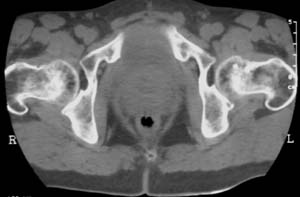

男,61岁,左侧髋关节疼痛,负重后更明显

现上传ct片

左侧股骨头增密,其内见有囊变密度减低区,关节面骨质硬化,关节间隙及髋臼无异示。考虑股骨头缺血坏死可能。建议mri检查。

我觉得股骨头未见到明显的问题,左侧股骨颈有卵圆形高密度影,考虑骨岛或骨梗死。

1\\左侧股骨颈有卵圆形高密度影,考虑骨岛或骨梗死。2\\由于临床症状疼痛,应该mri检查排除早期股骨头缺血坏死

左侧股骨颈处一卵圆形密度增高影,边界清,临近骨组织未见明显破坏.考虑为骨梗死,骨岛?